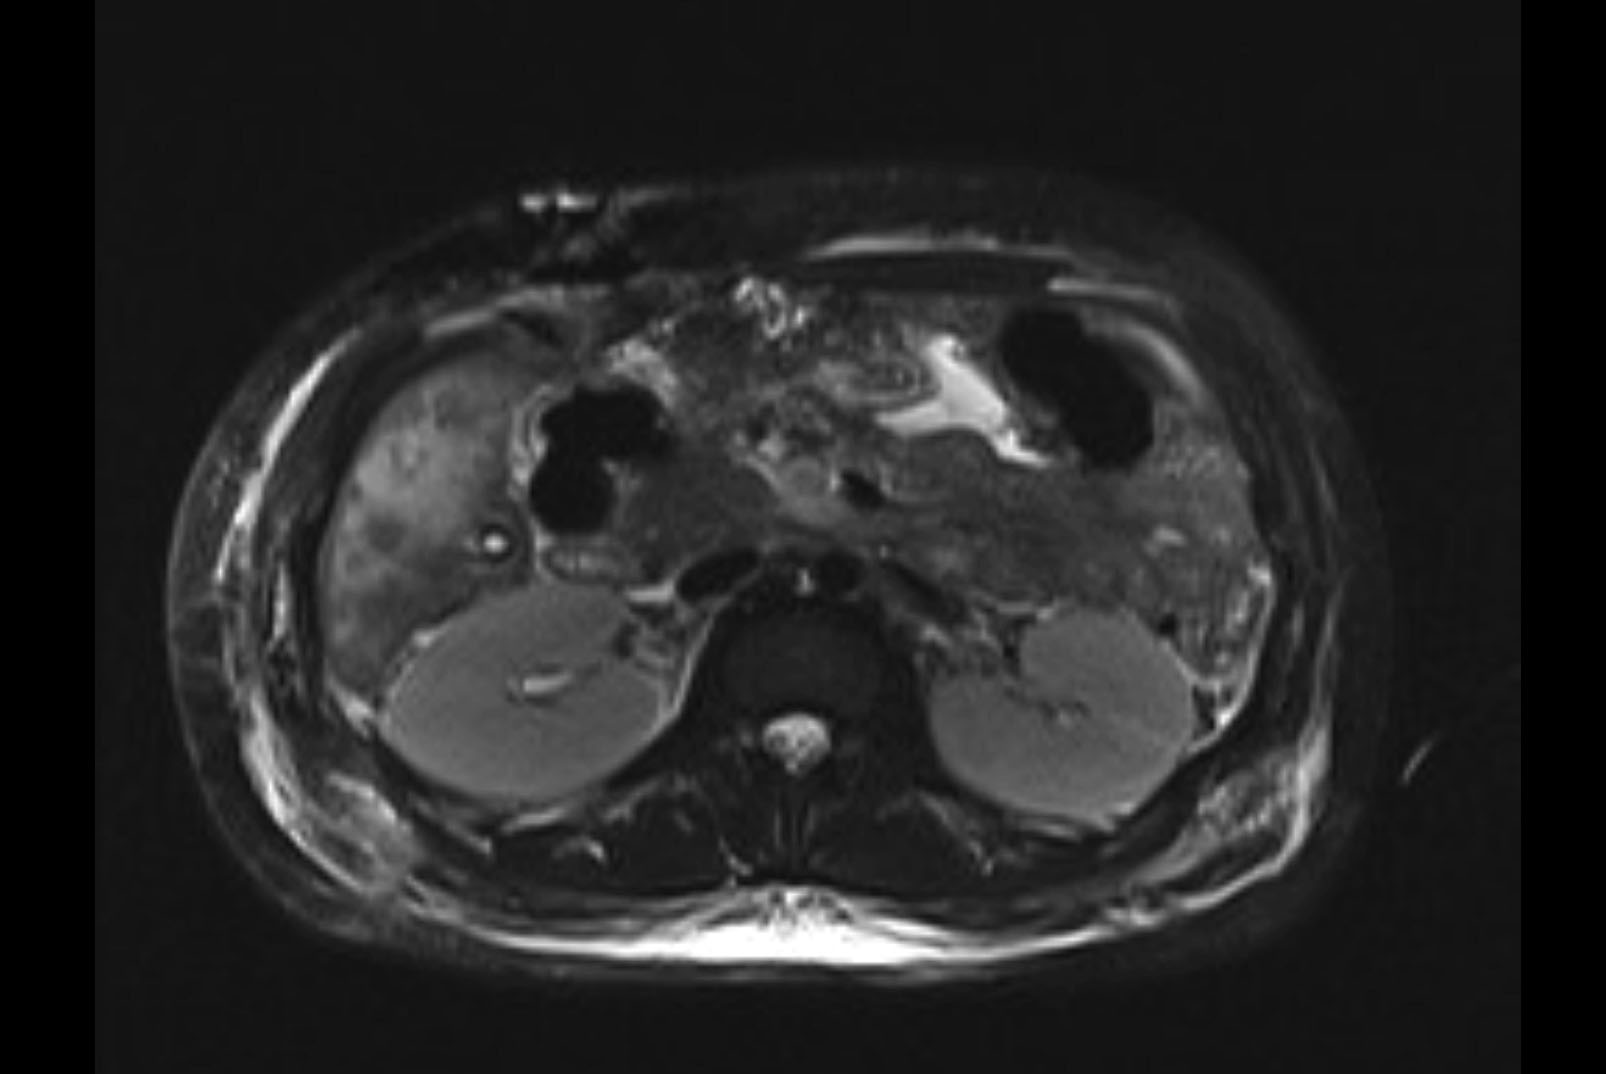

MRI T1

MRI T2